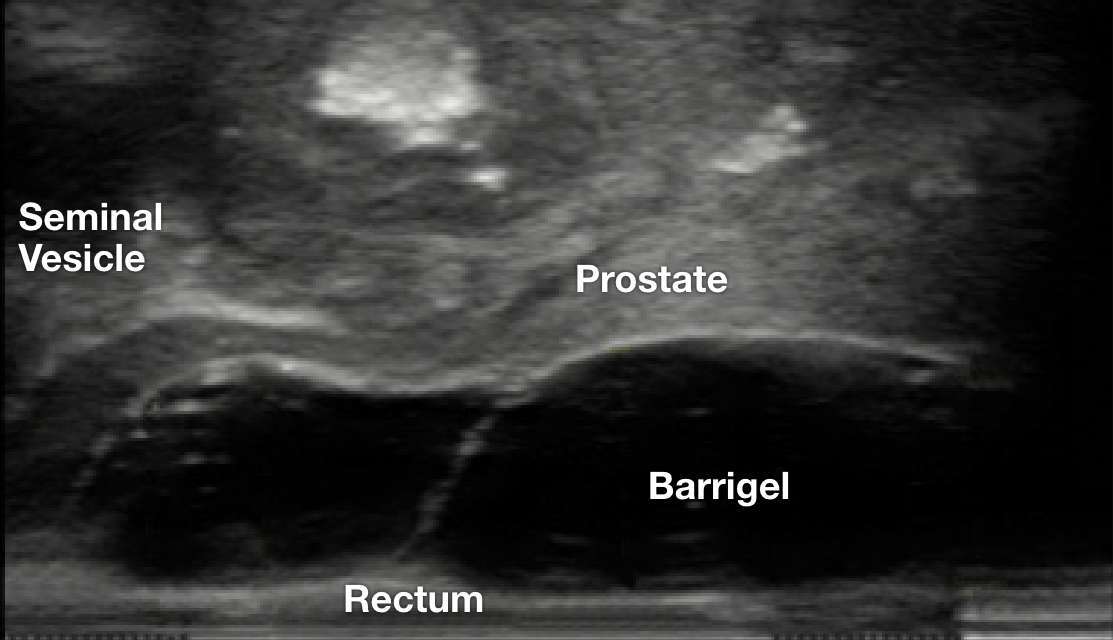

TRUS IMAGES

TRUS image courtesy of Rizwan Nurani, MD

Radiation Oncologist; California, United States